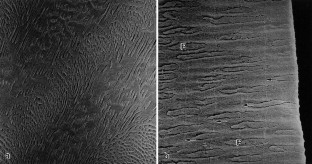

We studied the structural changes in the enamel of mandibular third molars of miniature pigs administered a daily oral dose of 2 mg NaF (approximately 0.9 mg of fluoride) per kg body weight (added to the feed) for 1 year. The treatment period covered most of the secretory stage and the entire post-secretory stage of amelogenesis of the M3. The enamel of the molars from the fluoride-fed pigs appeared opaque and chalky, and the erupted portions were stained brown. The underlying histopathological change was a pronounced subsurface hypomineralization of the enamel beneath a thin surface rim of higher mineral content. This enamel hypomineralization was attributed to a fluoride-induced impairment of the process of enamel maturation. The most conspicuous finding in the fluorotic enamel was the presence of numerous pit-type hypoplastic defects, denoting a marked fluoride-induced disturbance also of the secretory stage of amelogenesis. Microradiography and scanning electron microscopy revealed an enhanced incremental pattern in the outer enamel of the fluorotic molars. Typically, the bottom of larger hypoplastic defects was underlain by a broad, grossly accentuated incremental line. Occurrence of larger hypoplasias was further associated with the presence of aprismatic enamel, the formation of which was attributed to a loss of the prism-forming (distal) portion of the Tomes’ processes of secretory ameloblasts. The findings in the miniature pigs closely parallel earlier observations on fluorotic enamel of free-ranging deer and wild boar from fluoride-polluted areas.

Fig. 5a,b